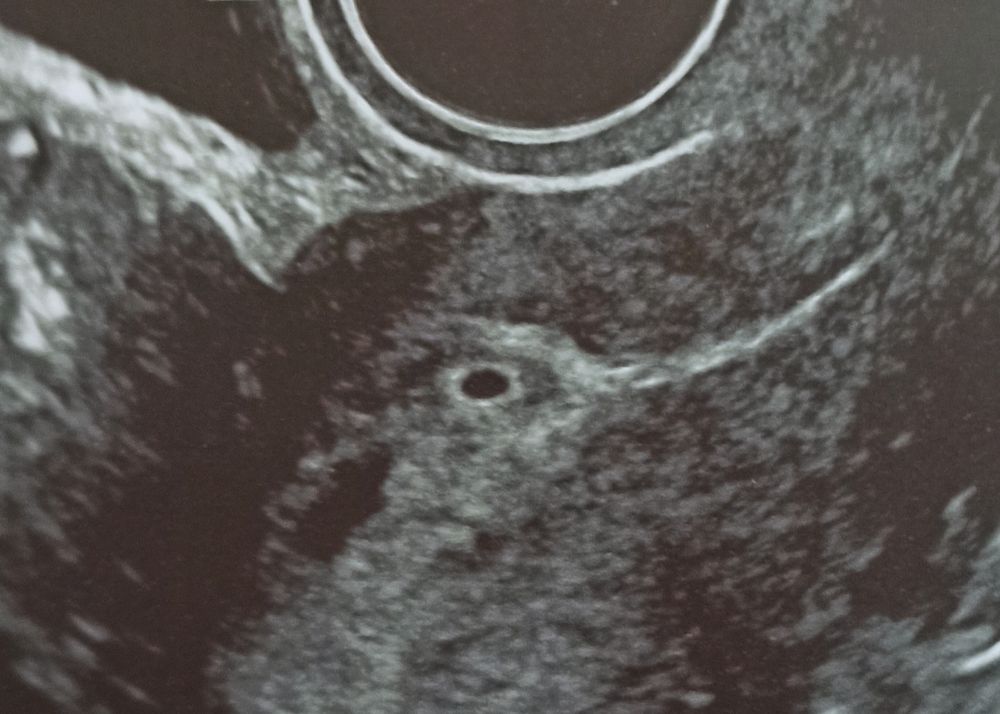

ХГЧ на 18 дпо-1352, УЗИ ПЯ 2,7❤

Сдам для интереса ещё на 21 и 25 дпо. Плодное яичко 2,7 мм, соответствует сроку гестации. Киста ЖТ большевата 33*29 мм, но не критично, рассосется, когда плацента вырастит, и снова в правом яичнике, как и все беременности с дочками, видимо мой рабочий яичник. Срок М сказала раньше, потому что была ранняя О на 10 день цикла, чтобы не было расхождений. Слава Богу, что не два плодных яйца, чего я очень боялась 😱👶👶